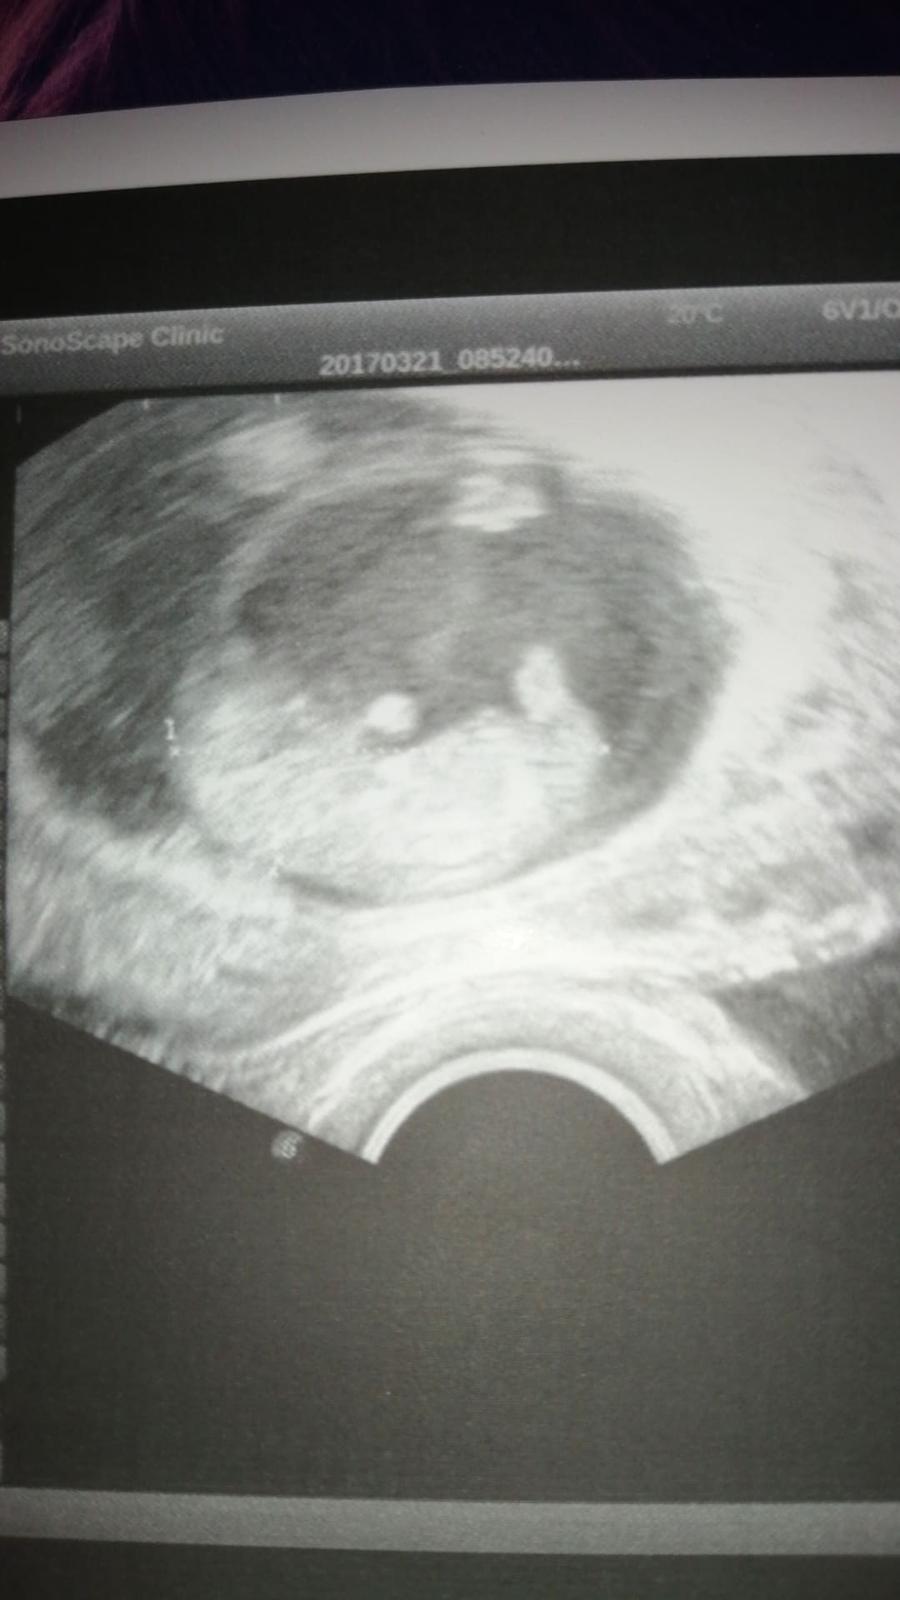

@vero987nika prvni fotka začátek 10tt druhá fotka 4tt